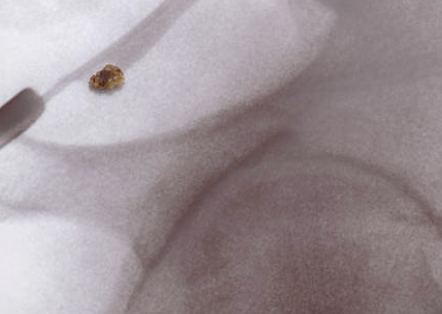

요로 결석은 콩팥, 요관, 방광, 요도 등에서 결석이 생기는 질환을 말합니다. 대부분의 경우, 소변 내에 있는 노폐물이 침전하여 결석을 형성하게 됩니다. 이러한 결석이 발생하면, 요로관을 통과할 때 불편감이나 통증 등의 증상을 유발합니다.